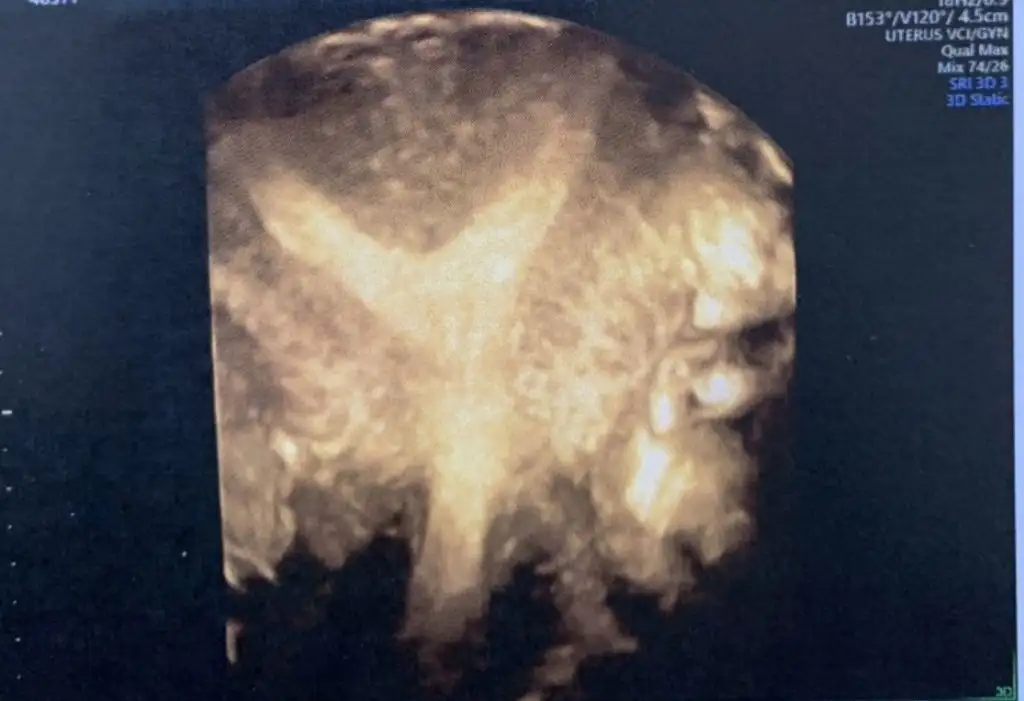

Rahmim bu şekildeydi.